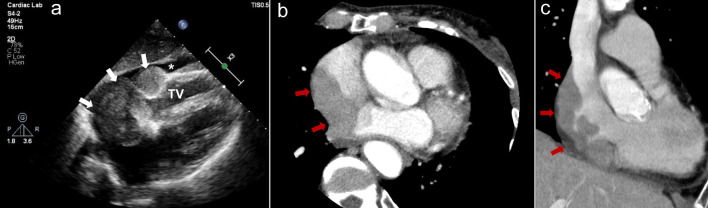

Primary cardiac lymphoma is a rare, often fatal malignancy that can cause disorders of conduction depending on tumor location. We report two cases with sick sinus syndrome and atrial flutter secondary to primary cardiac lymphoma originating from the right atrium. One case required pacemaker implantation in the chronic phase after complete remission of lymphoma, and the other case in the acute phase when cardiac mass occupied the right atrium. Depending on the disease activity of lymphoma including its size, growth rate, and degree of invasion, the clinical course of sinus node dysfunction varies between each patient. In patients with conduction disorders, we suggest that long-term cardiac monitoring is necessary not only at onset but also after complete remission of lymphoma.